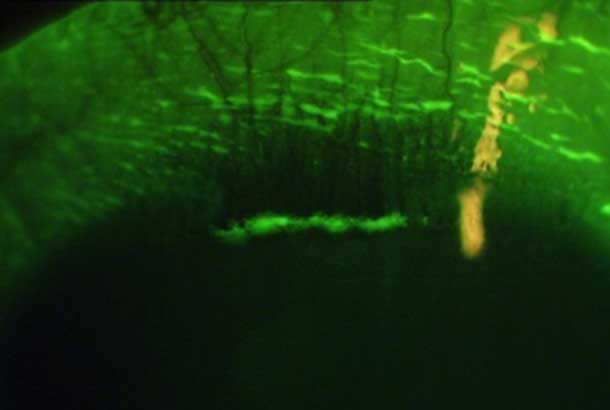

"id": 39,

"url": "https://cclm.media-doc.io/conditions/39/?format=api",

"name": "Vascularization – Superficial and Deep Stromal",

"category": "Cornea",

"detail": "<p>Neovascularization</p>\n\n<h2>Symptoms</h2>\n\n<ul>\n\t<li>None, but vision may be affected in deep stromal vascularization due to associated opacities &ndash; Superficial and Deep Stromal</li>\n</ul>\n\n<h2>Signs</h2>\n\n<ul>\n\t<li>Ingrowth of vessels in the cornea</li>\n\t<li>Usually superficial but can also be deep stromal</li>\n\t<li>Generally bilateral presentation</li>\n\t<li>Superficial: corneal penetration by vessels continuous with the limbal vessels</li>\n\t<li>Deep stromal: Blood vessel growth in the stroma and vessels disappear from view at the limbus</li>\n</ul>\n\n<h2>Etiology</h2>\n\n<ul>\n\t<li>Due to chronic corneal hypoxia</li>\n\t<li>Common sign associated with low Dk/t soft contact lens wear</li>\n\t<li>May be history of previous corneal disease, trauma, or infection</li>\n</ul>\n\n<h2>Prevalence</h2>\n\n<ul>\n\t<li>Rare with modern materials</li>\n</ul>\n\n<h2>Differential Diagnosis</h2>\n\n<ul>\n\t<li><a href=\"/condition/5\">Limbal Hyperemia</a></li>\n\t<li><a href=\"/condition/63\">See: Hyperemia Differential Diagnosis</a></li>\n</ul>\n\n<h2>Management</h2>\n\n<ul>\n\t<li>Consider SiHy lenses or GP lenses</li>\n</ul>",